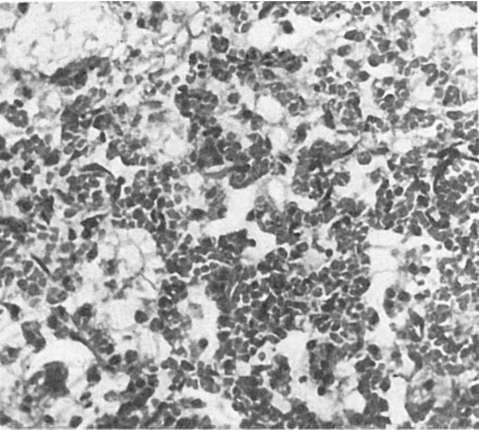

Рис. 251. Гриппозная

пневмония

телиальные клетки слущиваются на значительном протяжении в виде пластов, заполняя просвет бронхов, что ведет к развитию очагов ателектаза и острой эмфиземы легких. На фоне полнокровия, участков ателектаза и острой эмфиземы появляются очаги гриппозной пневмонии (рис. 251): в альвеолах видны серозный экссудат, альвеолярные макрофаги, десквамированные клетки альвеолярного эпителия, эритроциты, единичные нейтрофилы; межальвеолярные перегородки утолщены за счет пролиферации септальных клеток и инфильтрации

лимфоидными клетками, иногда обнаруживаются гиалиновые мембраны. В ряде случаев пневмония имеет характер геморрагической. В цитоплазме бронхиального и альвеолярного эпителия имеются включения вируса. Воспалительные, некробиотические и десквамативные процессы в легких сочетаются с регенераторными.